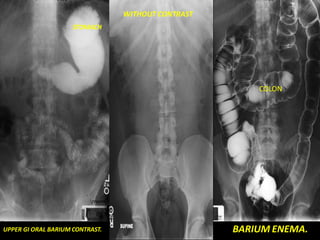

Fluoroscopy

• Dynamic radiography

–Permits real-time evaluation

of the gastrointestinal tract

– Barium Swallow (esophagus)

– Upper GI Series (stomach)

– Small Bowel Follow-through

– Barium Enema (colon)

• Barium (& air) is introduced

by enema or swallowing

•Barium appears white on the

images (high density

attenuates the x-ray beam)

•Can assess both intrinsic

(mucosal) and some extrinsic

(mass-effect) abnormalities.

WITHOUT CONTRAST

STOMACH

COLON

UPPER GI ORAL BARIUM CONTRAST. BARIUM ENEMA.

WITHOUT CONTRAST STOMACH COLON UPPER GIORAL BARIUM CONTRAST. BARIUM ENEMA.